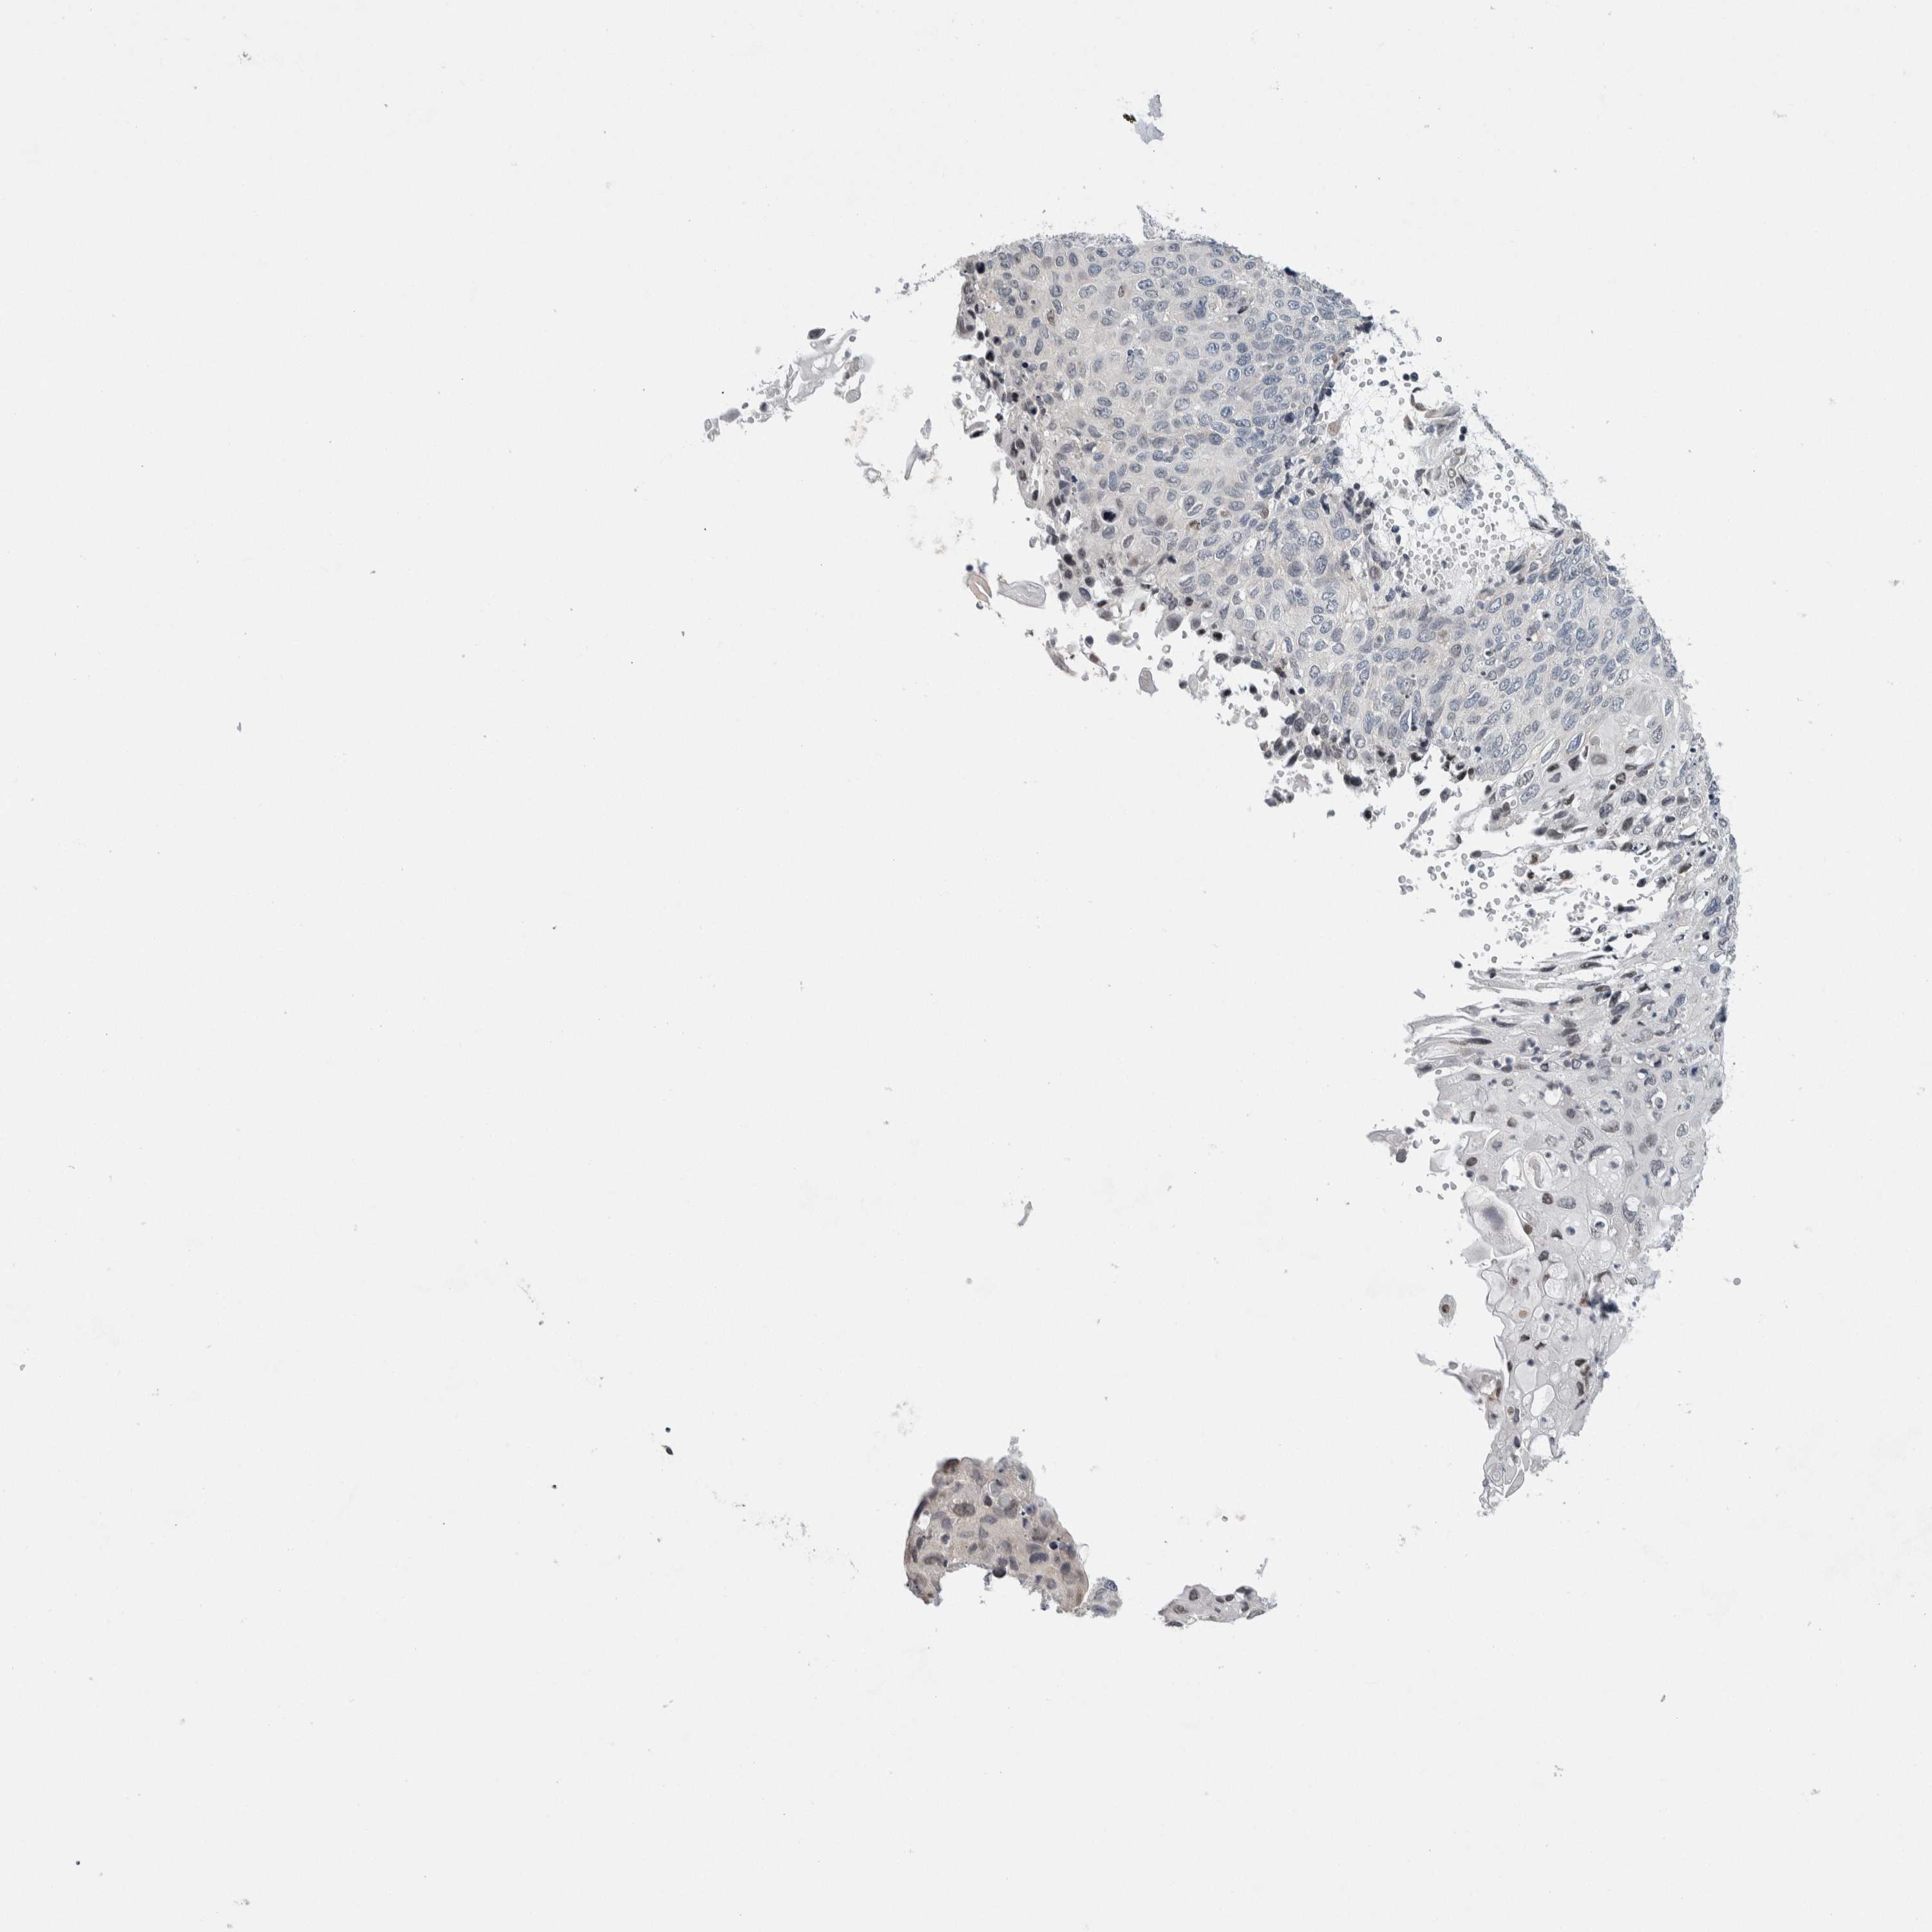

CERVICAL CANCER - Protein expressioni

A mouse-over function shows sample information and annotation data. Click on an image to view it in a full screen mode. Samples can be filtered based on level of antibody staining by selecting one or several of the following categories: high, medium, low and not detected. The assay and annotation is described here.

Note that samples used for immunohistochemistry by the Human Protein Atlas do not correspond to samples in the TCGA dataset.

Antibody stainingi

Antibody staining in the annotated cell types in the current human tissue is reported as not detected, low, medium, or high, based on conventional immunohistochemistry profiling in selected tissues. This score is based on the combination of the staining intensity and fraction of stained cells.

Each image is clickable and will lead to virtual microscopy that enables deeper exploration of all samples and also displays staining intensity scores, fraction scores and subcellular localization as well as patient and tissue information for each sample.

Antibody HPA003278

Antibody CAB022450

Staining

High

Medium

Low

Not detected

Intensity

Strong

Moderate

Weak

Negative

Quantity

>75%

75%-25%

<25%

None

Location

Nuclear

Cytoplasmic/membranous

Cytoplasmic/membranous,nuclear

Squamous cell carcinoma, NOS

Adenocarcinoma, NOS